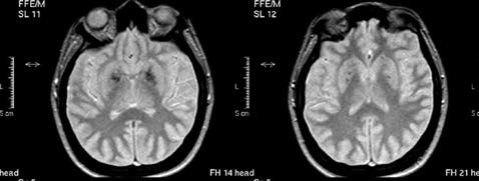

Resonancia magnética de encéfalo. Nota aclaratoria: corte axial, imagen potenciada en T1. Están marcadas las áreas hiperintensas que comprometen ganglios de la base, tálamo y coronas radiadas en forma bilateral

Figura 1: Resonancia magnética de encéfalo. Nota aclaratoria: corte axial, imagen potenciada en T1. Están marcadas las áreas hiperintensas que comprometen ganglios de la base, tálamo y coronas radiadas en forma bilateral

Fuente: elaboración propia